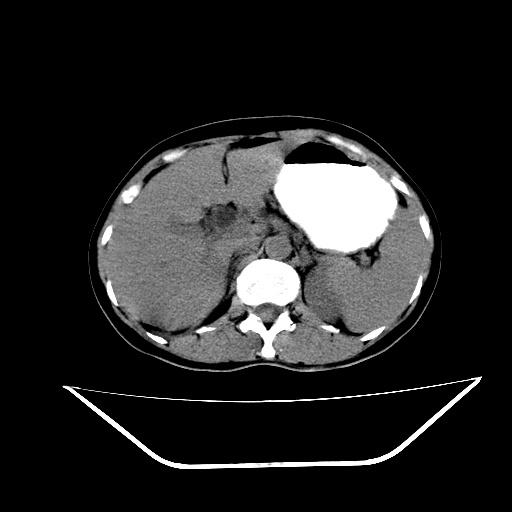

胰头占位ct讨论

胰头占位?(ct讨论)

红圈内为胰头占位病变,蓝圈内为胆总管.